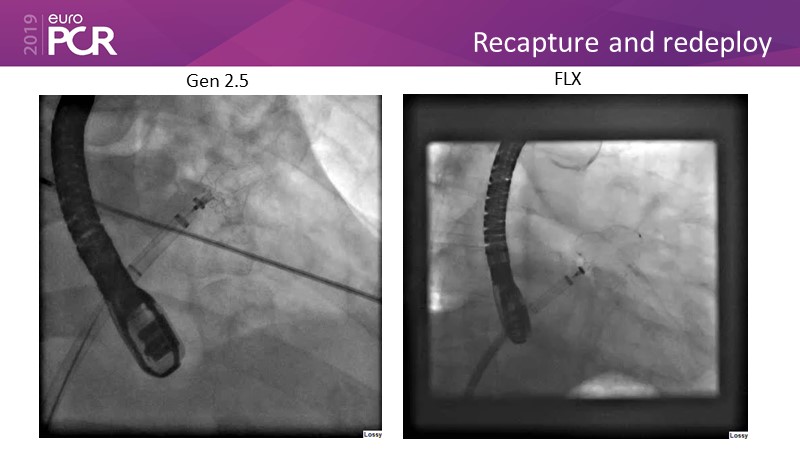

LAA closure

Left atrial appendage closure - A case-based discussion

Optimising procedural outcome and safety